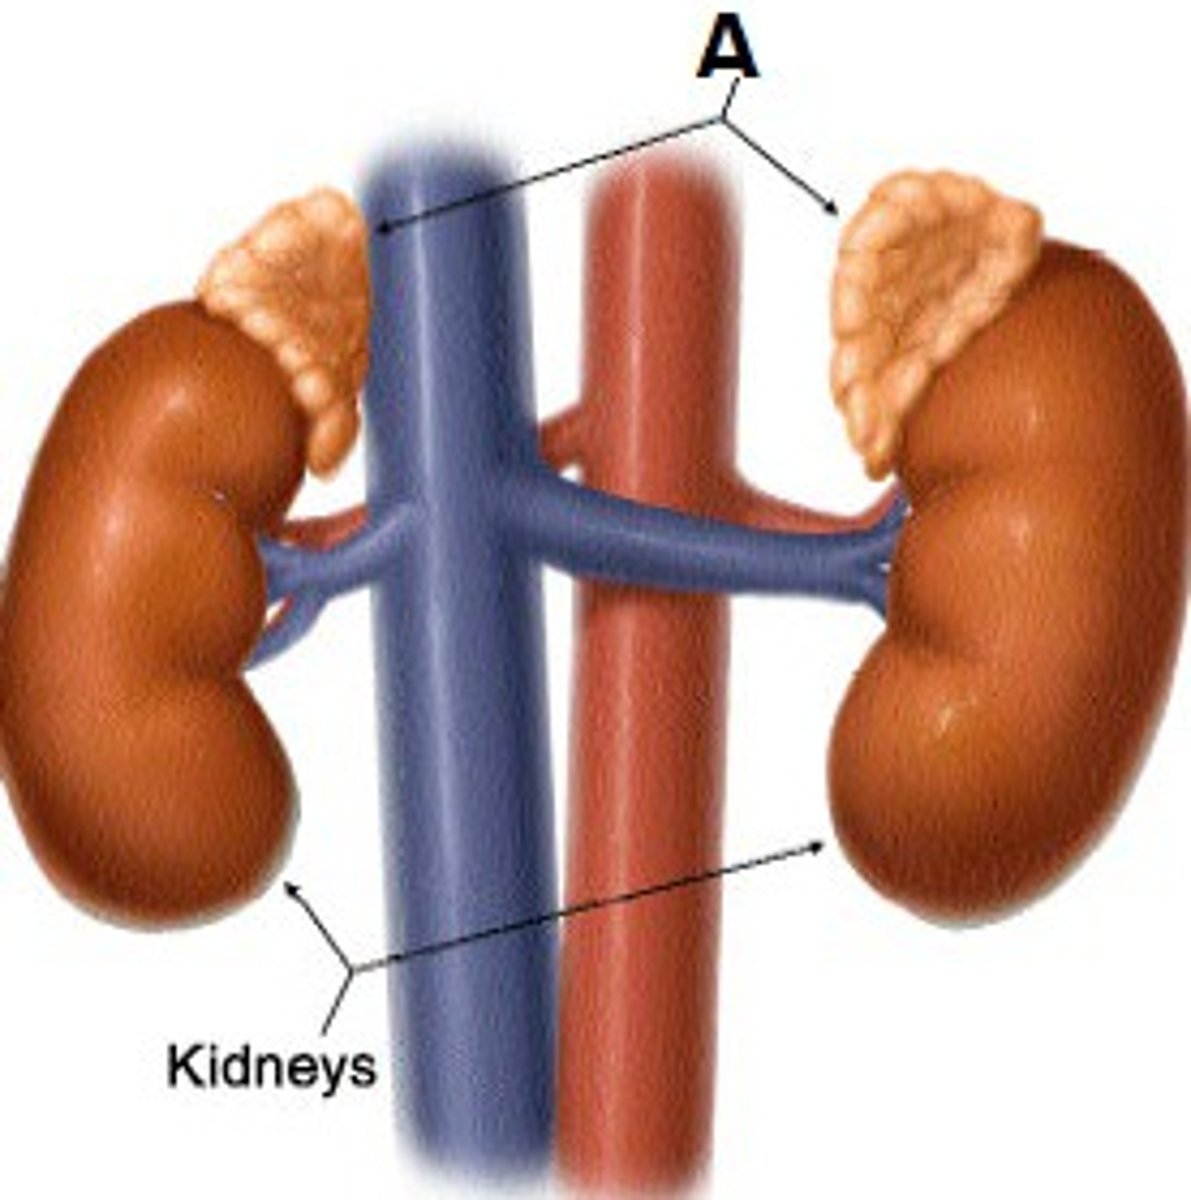

Adrenal Glands

a pair of endocrine glands that sit just above the kidneys

adrenal glands hormones

Epinephrine, norepinephrine, glucocorticoids- cortisol, mineralocorticoids- Aldosterone